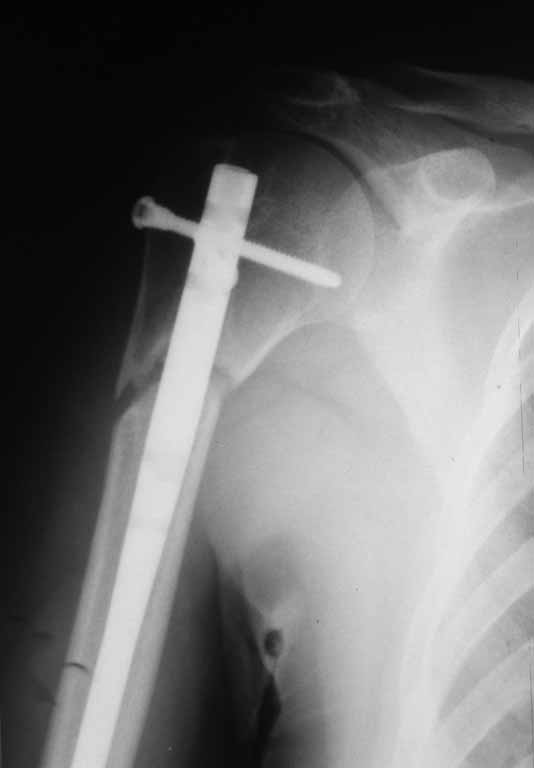

Ложный сустав проксимального плеча в условиях БИОС

Уважаемые коллеги представляю вашему вниманию пациентку 27 лет с ложным суставом проксимального отдела плечевой кости в условиях БИОС.

Травма 11 мес. назад в результате падения. У нас в клинике на 2-е сутки выполнена закрытая репозиция, БИОС плечевой кости.

После выписки наблюдалась в ЦРБ по м\ж. Спустя такое большое количество времени направлена к нам для контрольного осмотра с жалобами на умеренный болевой синдром. На контрольных рентгенограммах имеются признаки ложного сустава проксимального отдела плечевой кости. Пациентка запланирована на госпитализацию.Прошу совета в тактике оперативного лечения.

На этом снимке результат дистракции, а происхождение дистракции без полного снимка плеча трудно увидеть. (насчет стандартных снимков писали неоднократно, но по-прежнему показывают короткие снимки без захвата даже всей длины имплантата) Дистракция обычно происходит, когда длинный гвоздь упирается в узкой части в дистальном отделе, или при отсутствии дистальной блокировки, когда отломок скользит по гвоздю.